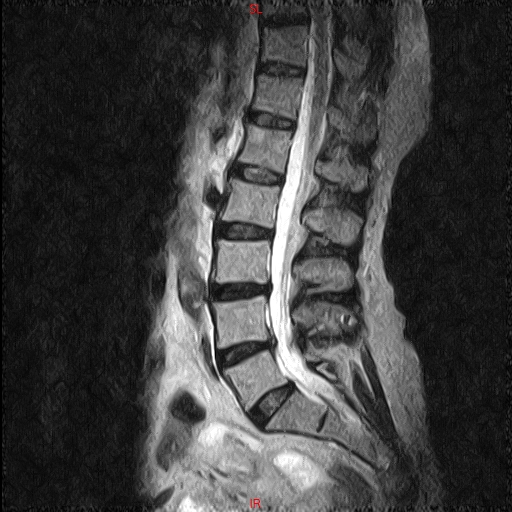

• Resonancia PATOLÓGICA DE C.LUMBAR - HERNIA DE DISCO L5-S1 -  SAG T2